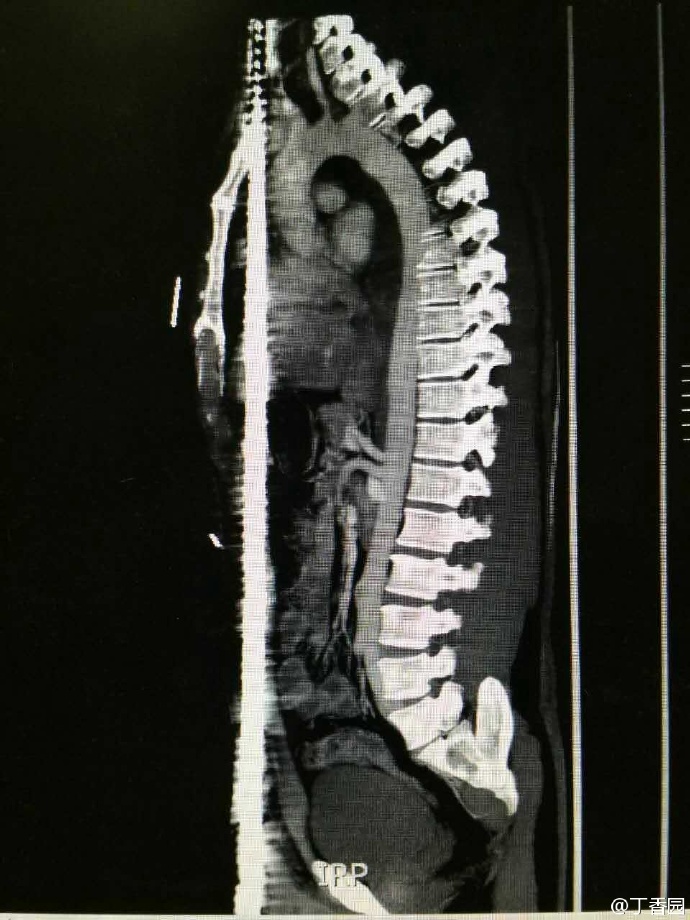

齐鲁医院的病例——正中贯通伤

001.jpg (67.8 KB)

001.jpg